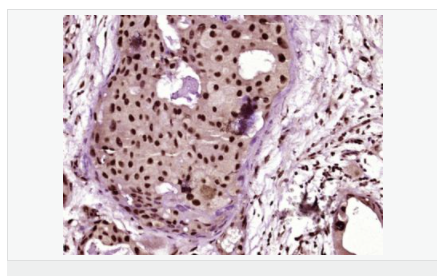

產(chǎn)品應用ELISA=1:5000-10000 IHC-F=1:100-500 ICC=1:100-500 IF=1:100-500 (石蠟切片需做抗原修復)

image.png